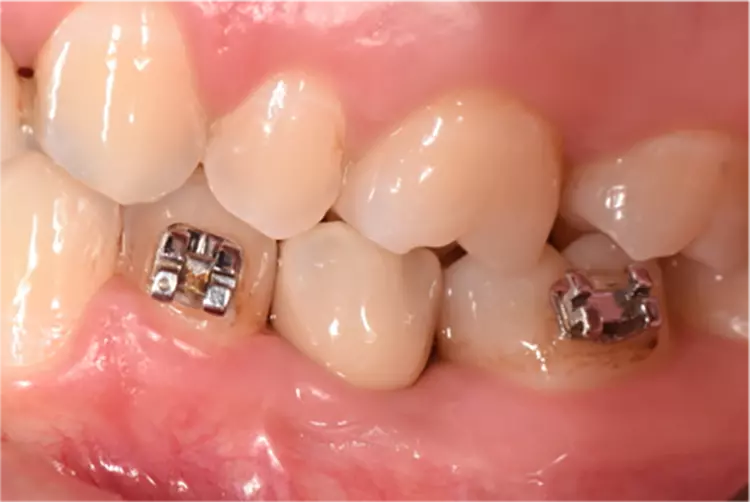

Die Implantate wurden im üblichen chirurgischen Vorgehen inseriert und sofort mit einem Provisorium aus Polymethylmethacrylat (CAD-Temp, VITA) versorgt, wobei die Provisorien außer Okklusion geschliffen wurden und darauf geachtet wurde, dass approximal nur sehr schwache Kontakte bestanden (Abb. 3a bis e). Die definitive prothetische Versorgung erfolgte im Unterkiefer nach frühestens 2 Monaten, im Oberkiefer nach frühestens 4 Monaten. Die Restaurationen wurden aus verblendetem Zirkonoxid hergestellt (VITA YZ HT / VITA VM 9, VITA).

Bei Knochendefekten ist eine Augmentation erforderlich. In der klinischen Studie „FR/ZH“ wurden in 11 Fällen kleinere simultane Augmentationen durchgeführt (vergl. Abb. 3). Die Augmentationen dürfen aufgrund der ermittelten Sondiertiefen und Röntgenbefunde als erfolgreich angesehen werden.